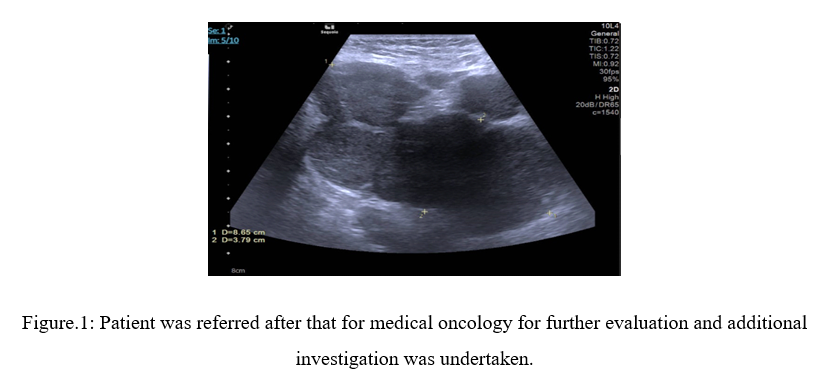

A PET scan of the chest, abdomen, and pelvis was also performed. The scan identified multiple enlarged and abnormally hypermetabolic, matted lymph nodes in the right axillary levels 1 and 2. These nodes showed relatively stable metallic activity, possibly related to prior injections. However, the scan also revealed multiple new lesions extending into the adjacent subcutaneous tissue, potentially involving the thickened skin. Additionally, infiltration of the pectoralis major and minor muscles was observed. The largest right axillary lymph node measured 4.5 x 6.2 cm with a standardized uptake value (SUV) of 9.6.

Importantly, the PET scan did not detect any hypermetabolic lymph nodes below the diaphragm (infradiaphragmatic) or evidence of extranodal hypermetabolic disease .Based on this pattern, the findings are suggestive of stage II lymphoma.

Figure 3, Figure 4